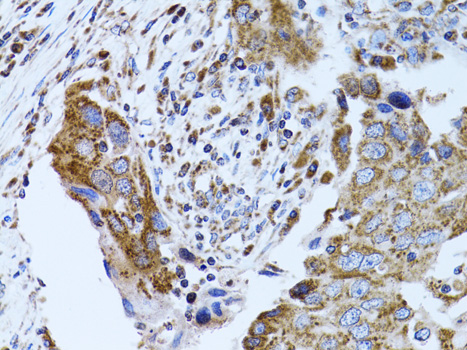

Immunohistochemistry of paraffin-embedded human breast cancer using FABP4 at dilution of 1:100 (40x lens).